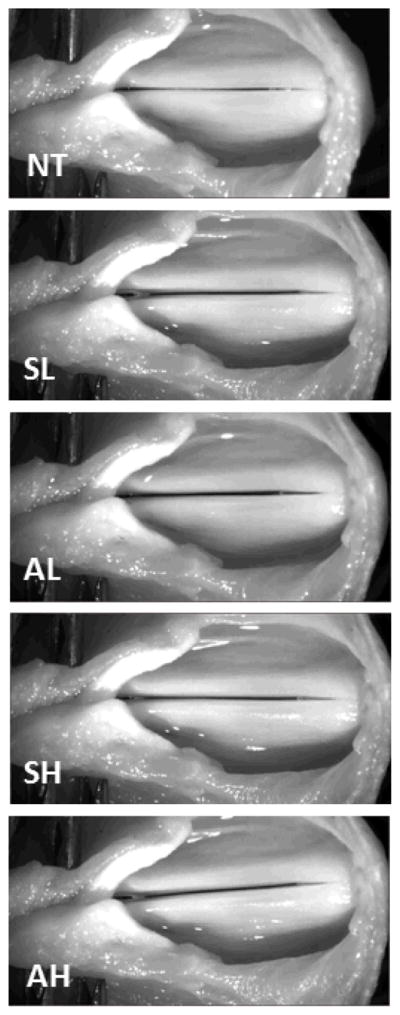

Figure 4.

Superior view of larynx across conditions. Larynx is slightly rotated with asymmetrical light tension and more severely rotated with asymmetrical heavy tension. NT = no tension; SL = symmetrical light tension; AL = asymmetrical light tension; SH = symmetrical heavy tension; AH = asymmetrical heavy tension. Left cricothyroid muscle paralysis is simulated in AL and AH.